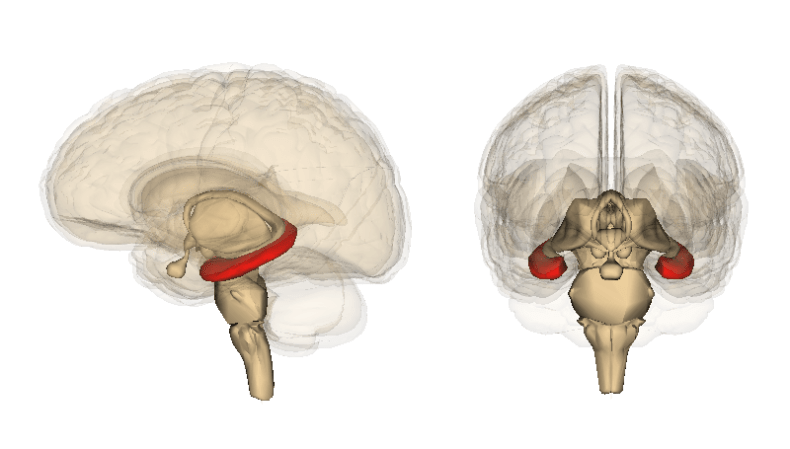

We have two hippocampi in our brains, one on the left, the other on the right. It’s one hippocampus and two hippocampi. Hippocampus is Latin for seahorse. Consequently, in cross-section, a hippocampus looks like the curled tail of a seahorse. Our neural seahorses are to be found in the medial portion of our temporal lobes, as shown in the figure below. The brain’s seahorses play a crucial role in forming memories. Additionally, the hippocampi play a prominent role in mood, stress and emotional resilience. Importantly, a large body of MRI studies has shown that longer or repeated depressive episodes are linked with progressive hippocampal shrinkage. In the brain, shrinkage or volume loss is also called atrophy.